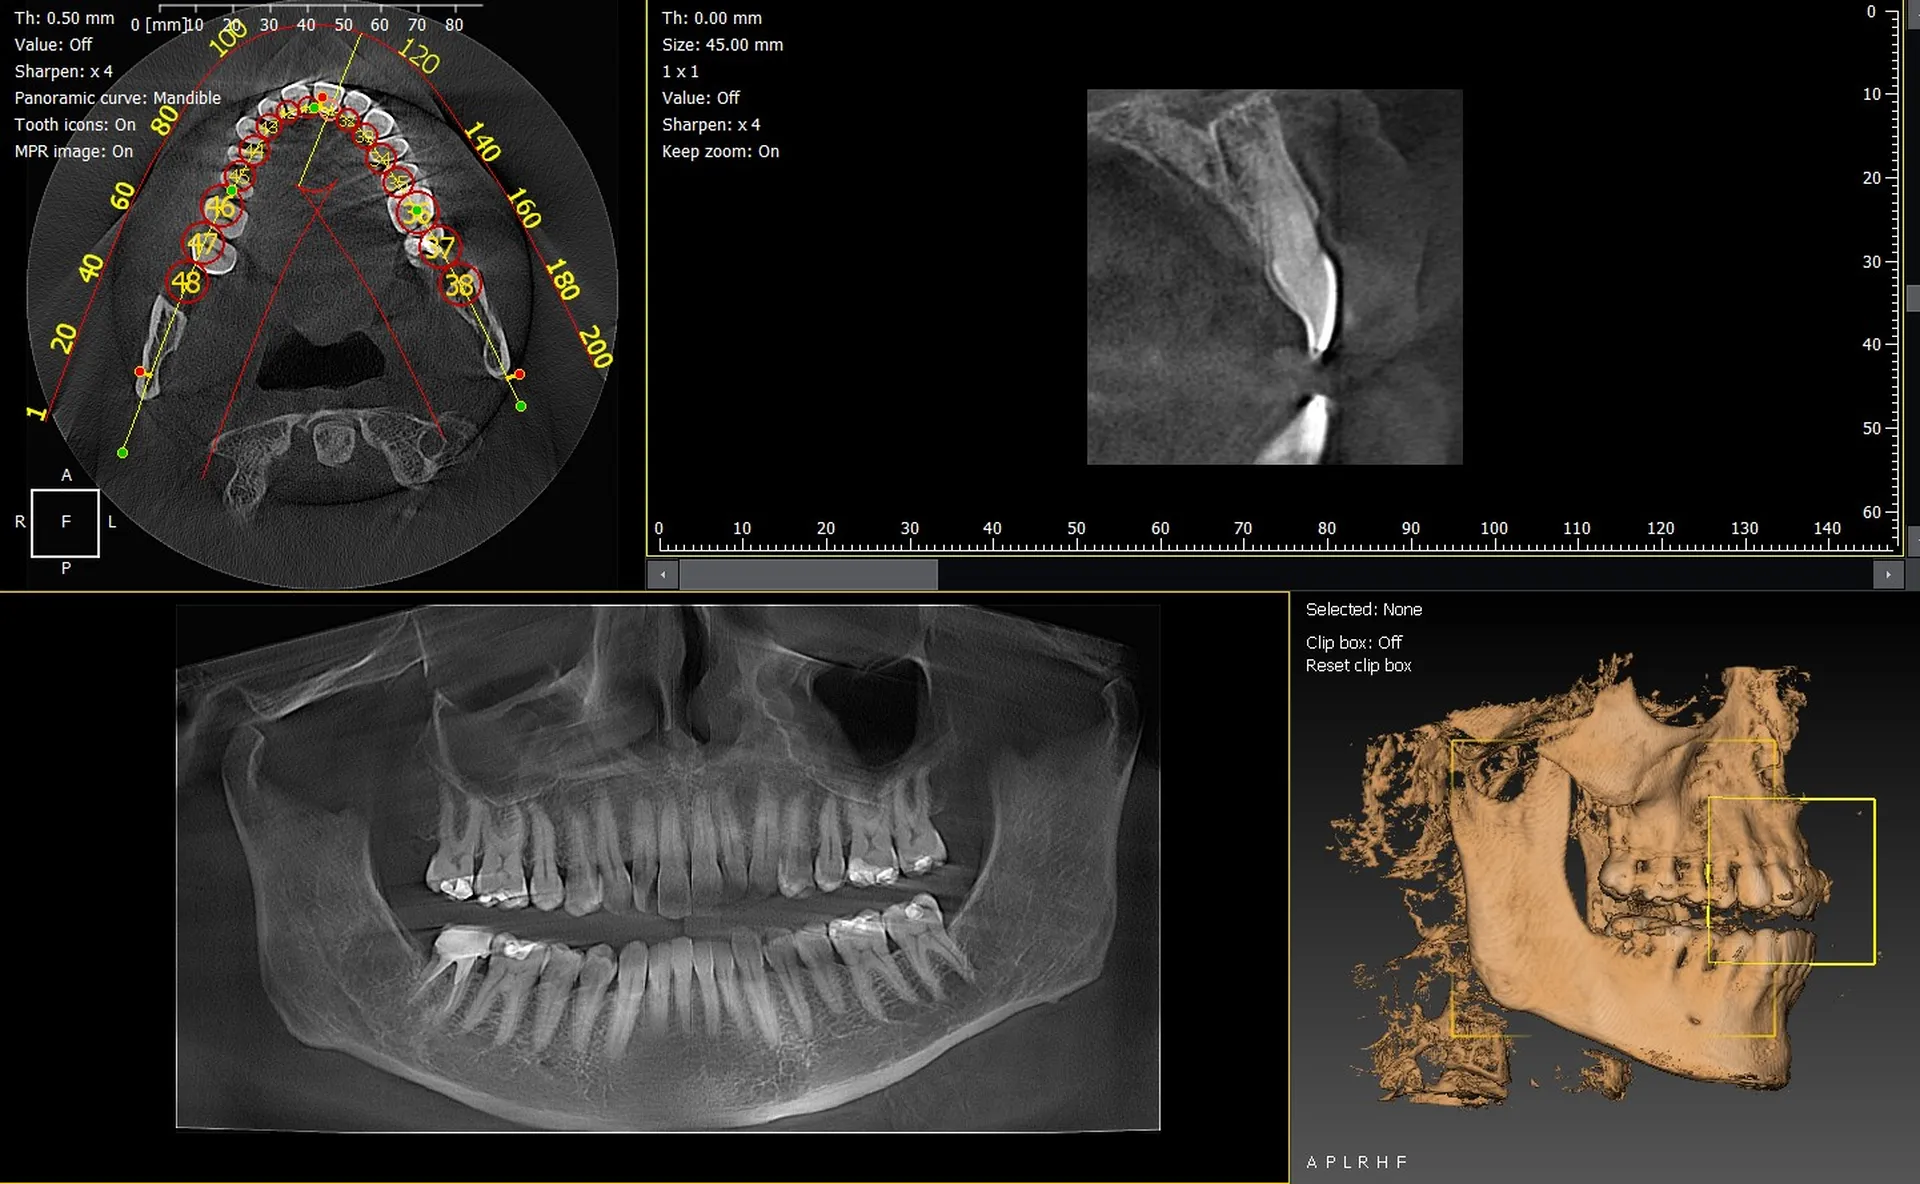

Les cabinets dentaires de Menton et du département des Alpes-Maritimes (06) modernisent leur plateau technique afin d’offrir des diagnostics plus rapides et plus précis. Parmi les solutions d’imagerie les plus performantes, les panoramiques CBCT 3D VistaVox de Dürr Dental et l’Owandy I-Max 3D s’imposent comme des équipements fiables, adaptés aux besoins cliniques actuels.

VistaVox 3D : précision et champ adapté

Le VistaVox offre un volume d’imagerie conçu pour l’arcade dentaire, idéal pour :

• l’implantologie,

• l’endodontie,

• la chirurgie orale,

• le diagnostic des ATM.

Sa résolution élevée et son positionnement simplifié améliorent la fiabilité des examens.

I-Max 3D : compact, moderne et polyvalent

L’Owandy I-Max se distingue par :

• son design mural compact,

• son excellente qualité d’image en 2D et 3D,

• une installation rapide,

• une interface intuitive pour l’équipe soignante.

C’est une solution idéale pour les cabinets urbains de Menton cherchant un appareil performant sans contrainte d’espace.